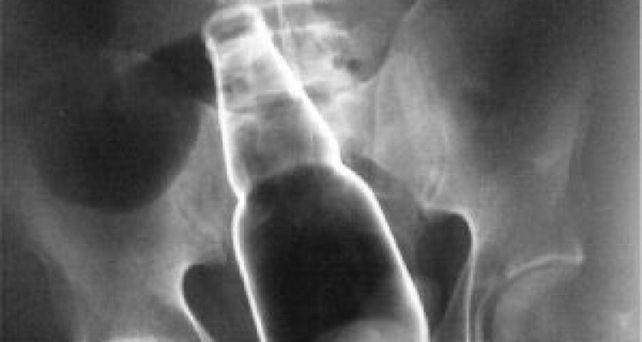

Un hombre en Catamarca agredió salvajemente a su yerno luego de que éste abusara sexualmente de otra hija del atacante. El sujeto le introdujo una botella en el ano al hombre y aseguró que "se hizo justicia".

Según informó el diario La Unión, todo comenzó cuando la madre de la adolescente de 15 años denunció que el marido de su otra hija había violado a la menor. Al enterarse de lo ocurrido, el padre de la joven fue en busca del depravado y no sólo lo golpeó, sino que también introdujo un elemento contundente en sus partes íntimas.

Una vez en su celda, el sujeto aseguró que su suegro lo "violó con una botella". La policía puso en conocimiento del fiscal Jorge Flores, quien pidió la detención del hombre.